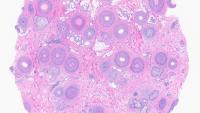

Take the first step towards a rewarding career in Dermatopathology by enrolling in Columbia University Irving Medical Center/NewYork Presbyterian Hospital's comprehensive one-year ACGME-accredited fellowship program. Tailored for graduates of Dermatology or Pathology residencies, this intensive program delves into diverse disciplines including immunopathology, molecular dermatopathology, and genomics.